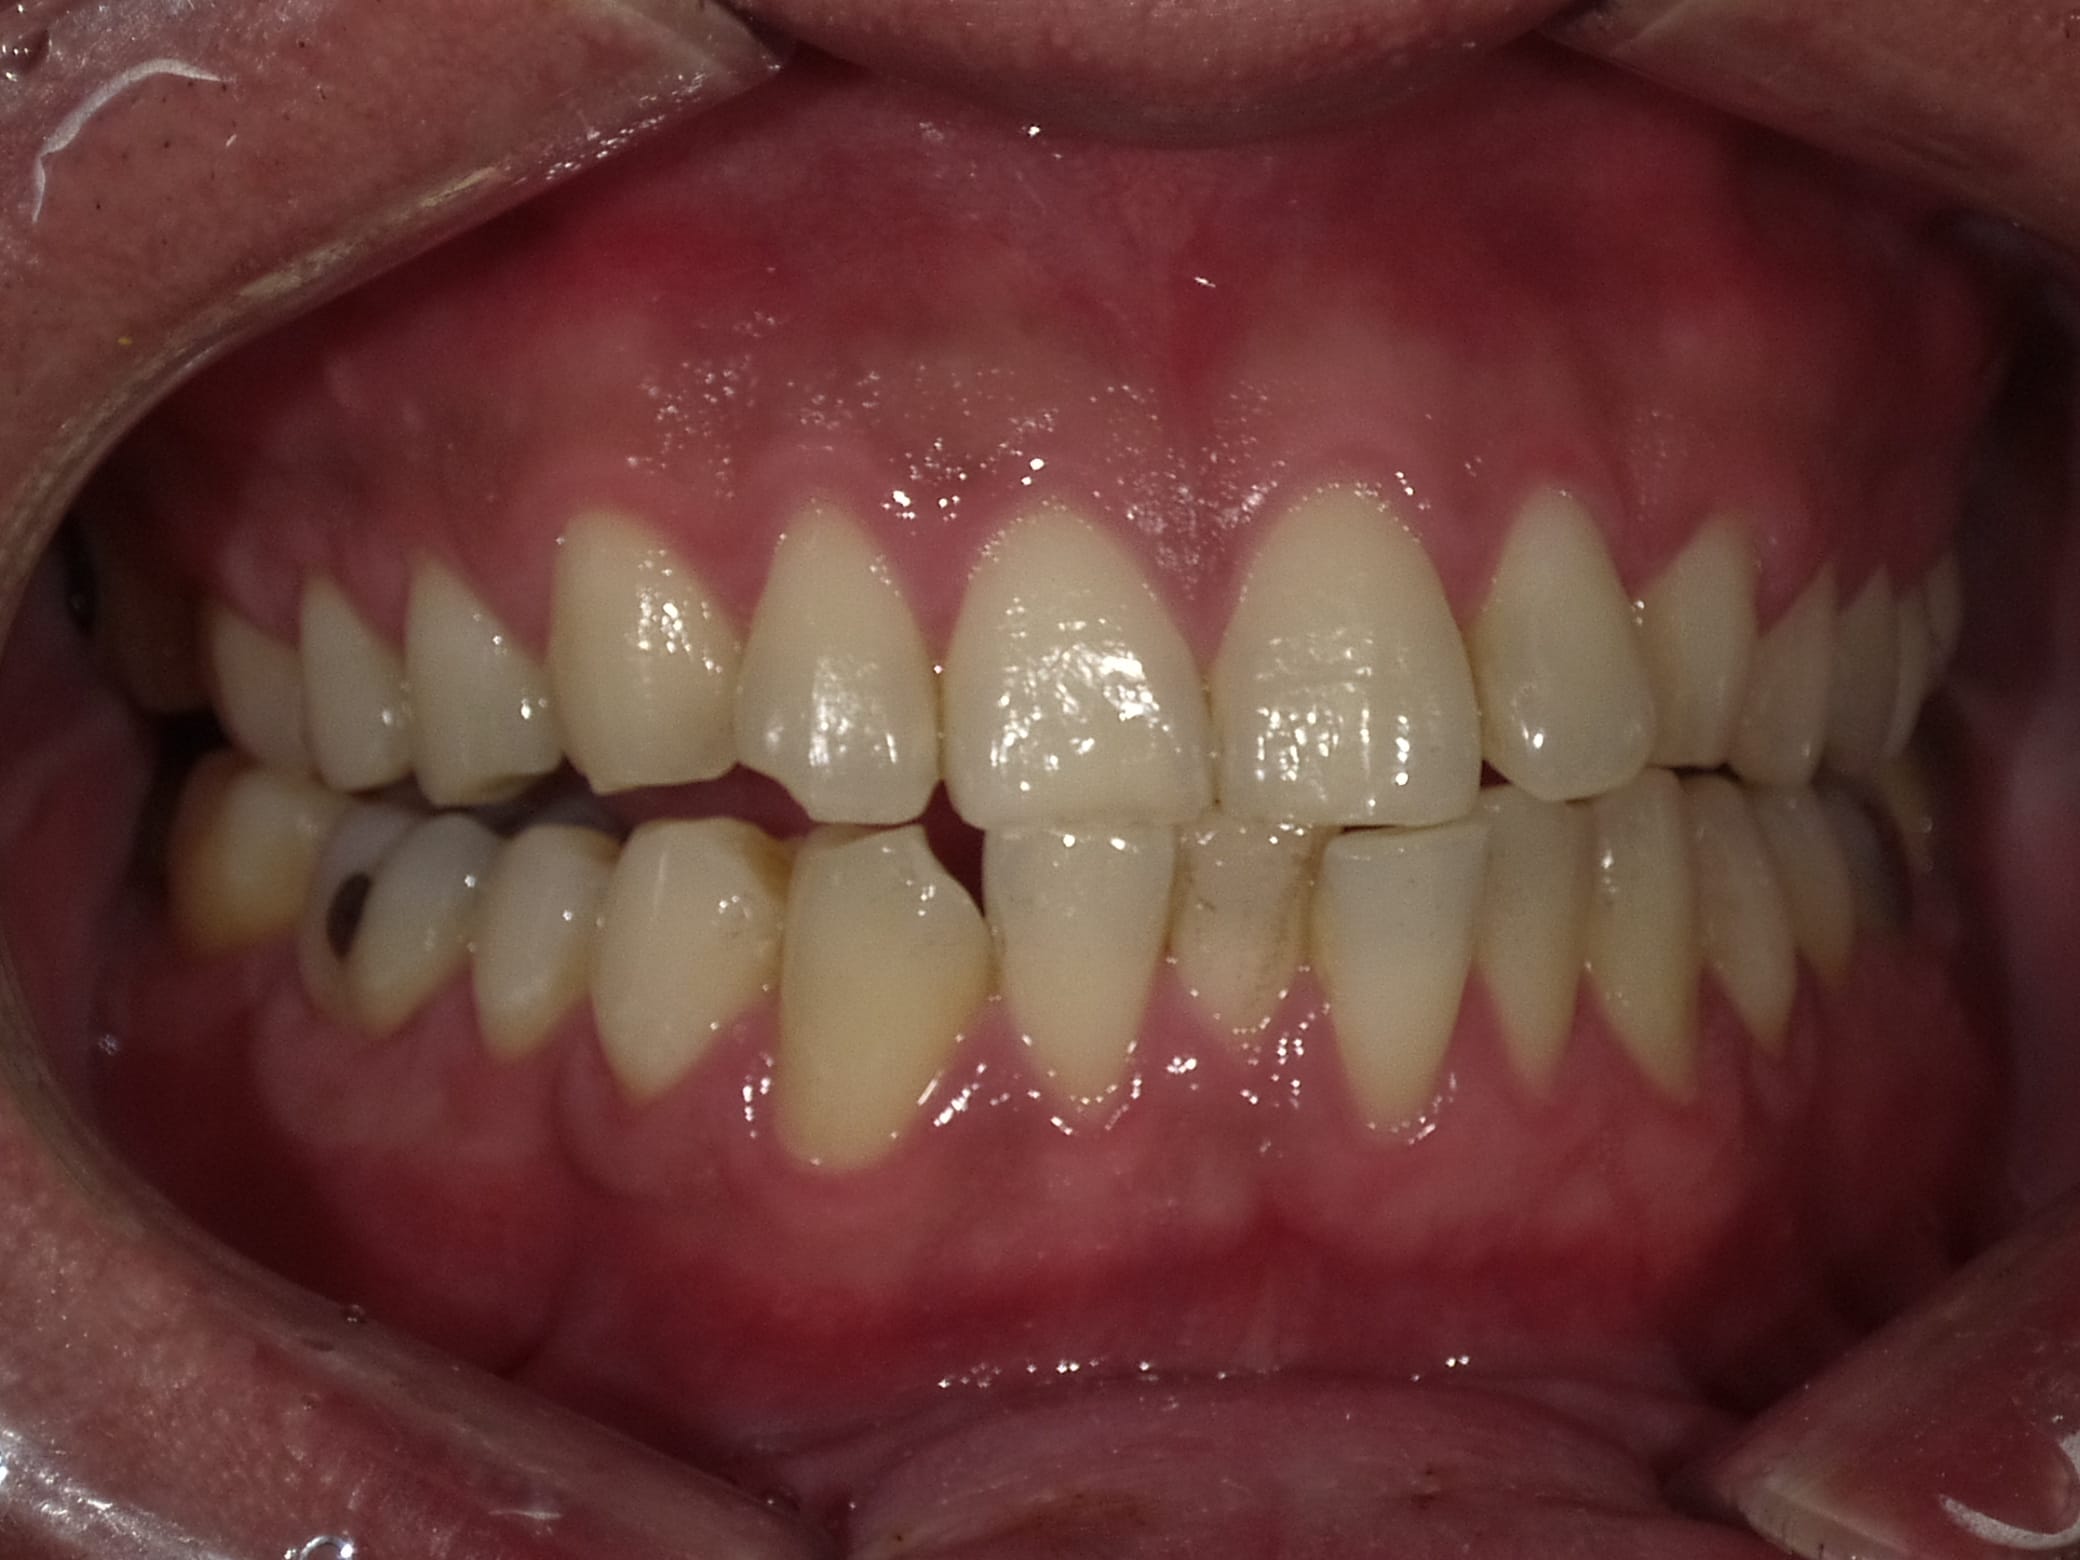

Case033

前歯が虫歯なのと、保険のプラスチックで大きく治療されていて色が悪いこと、歯並びが出っ歯気味であることを気にしてセラミックにしたいという主訴で来院された患者様です。

虫歯が大きかったところは神経治療をきちんと行い、

初診時を含めてトータル4回のご来院で完了です。

今回は前歯を下げる、歯列を整える、白すぎず自然に綺麗に見える色というご希望に沿って治療しました。

ご興味のある方はいつでもご相談ください。

担当 理事長 佐藤 悠野